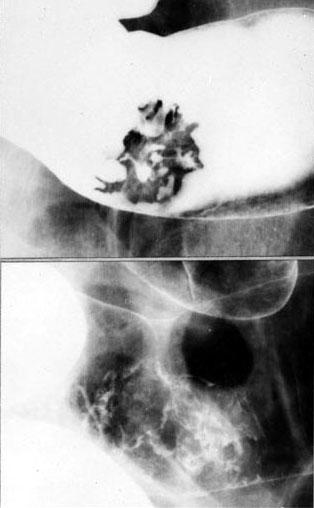

部位(按器官分)大肠/乙状结肠

检查方法X线

肿瘤的肉眼分类0型(表在型)/I型(Is)

肿瘤最大直径35~40

肿瘤的深度sm